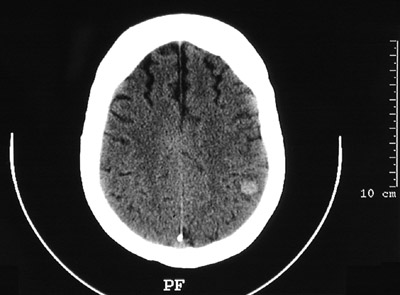

| There is a solitary metastasis in the superior left parietal lobe peripherally in the region of the grey-white matter junction which is bright on this CT scan of the head. In a middle aged to older adult, a solitary metastasis must be distinguished from a primary glioma. The most common sites for primary neoplasms metastatic to brain include lung, breast, and kidney. |